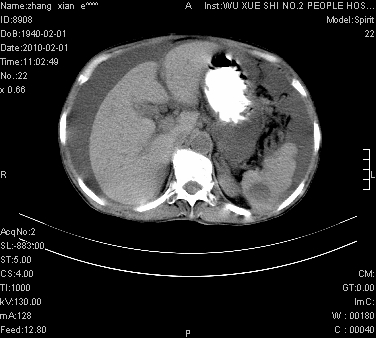

标题: CT24434:70岁 女 腹胀,腹水原因待查 [打印本页]

标题: CT24434:70岁 女 腹胀,腹水原因待查

大量腹水,脾脏囊性占位,子宫颈占位,右侧腹股沟淋巴结肿大,建议+c,先查妇科。

大量腹水,脾囊肿可能性大,建议增强

大量腹水,右肾、脾囊肿可能性大          考虑左侧附件区占位,建议增强